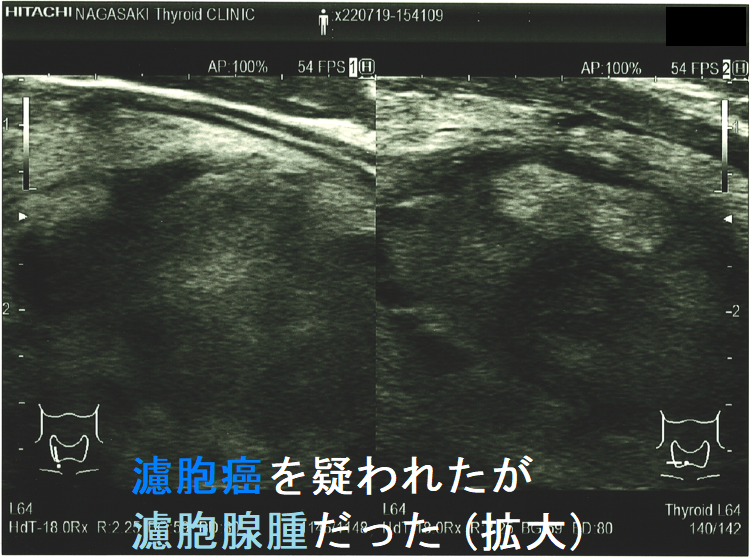

濾胞腺腫内の低エコー領域(コロイド産生が多い部分);濾胞腺腫内にやや低エコーな部分が存在。濾胞癌を疑って穿刺細胞診してみたら、コロイド産生の多い濾胞細胞が採れた。

そもそも、細胞診で良性濾胞腺腫と濾胞癌を鑑別するのは困難につき、例え良性判定でも注意を要します(内部に低エコー領域が存在する濾胞癌)

ケース①

ケース②

濾胞癌を疑われたが濾胞腺腫だった 超音波(エコー)画像;特に、中心部の極めて低エコーな箇所が疑わしい。。

実際、同じような見え方で甲状腺濾胞癌だったケースもあります(内部に低エコー領域が存在する甲状腺濾胞癌)。